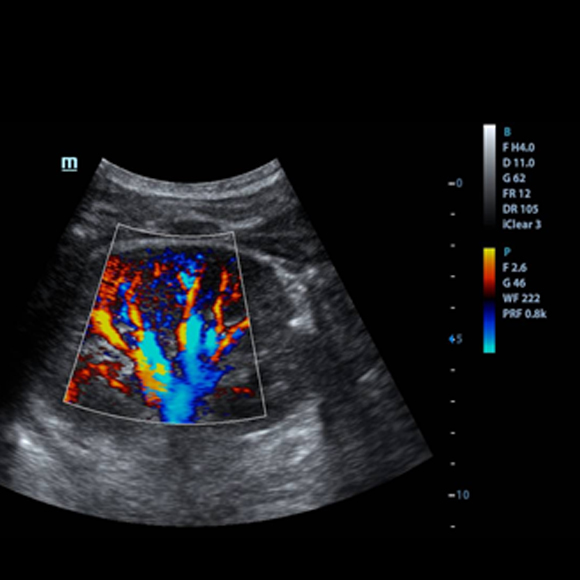

ECOGRAFÍAS DOPPLER

La ecografía Doppler es una ecografía a color, que en el caso de las mujeres embarazadas se utiliza para analizar el flujo de sangre que circula a través de las cavidades y las válvulas del corazón del bebé.

La ecografía vascular utiliza ondas sonoras para evaluar el sistema circulatorio del cuerpo y ayudar a identificar bloqueos en las arterias y venas, y a detectar coágulos de sangre. Este examen generalmente incluye un estudio de ultrasonido Doppler